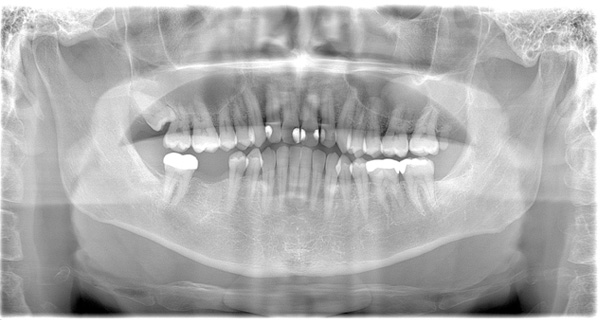

BEFORE

| 年代・性別 | 50代 女性 |

|---|---|

| 主訴 | 左上のブリッジがグラグラして外れそう |

| 治療期間 | 約18ヶ月 |

| 費用 | 1,600,000円 |

| 治療内容 | インプラント、骨造成、サイナスリフト、セラミック修復 |

| 治療に伴うリスク | インプラント周囲炎 セラミックの破折、脱離 |